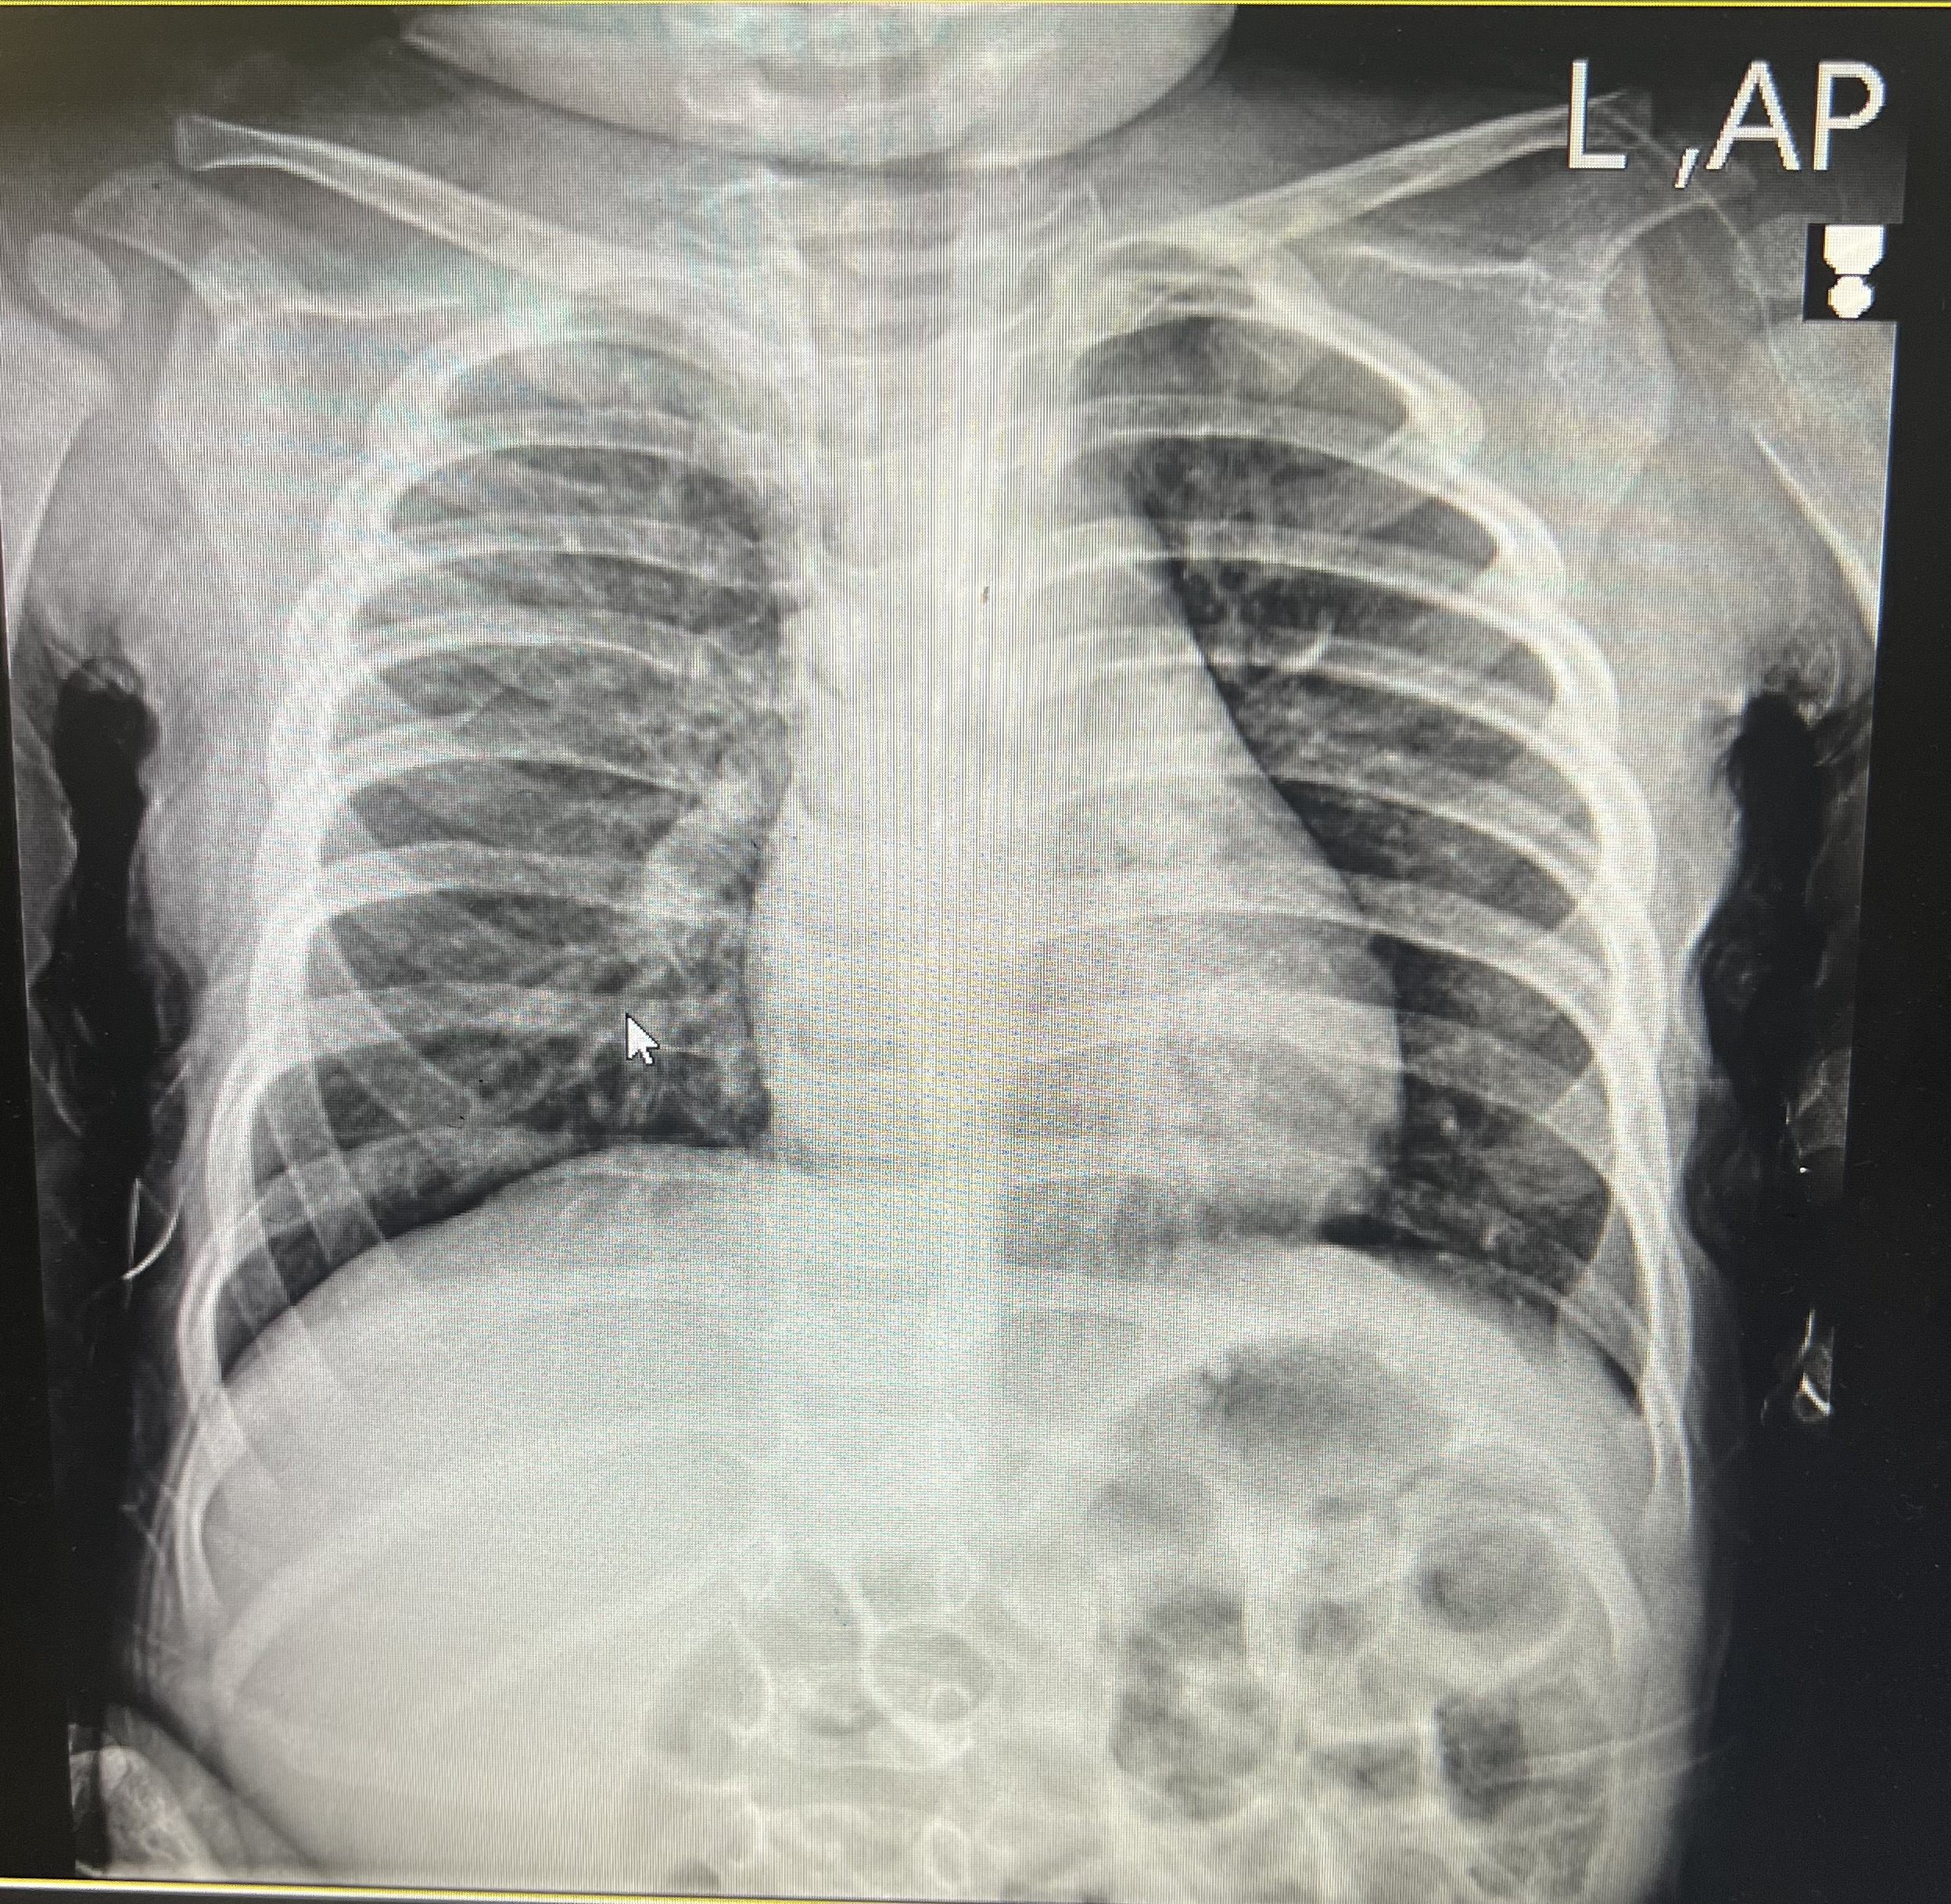

کودک ۱۰ ماهه که از ۳ روز گذشته دچار آبریزش بینی و سرفه و بی قراری شده که همراه با تب نبوده است با تشدید سرفه و تنگی نفس و رتراکشن و رال در تمامی زون های ریه راست و یک نوبت استفراغ شب گذشته به این مرکز مراجعه کرده است.

X-Ray: